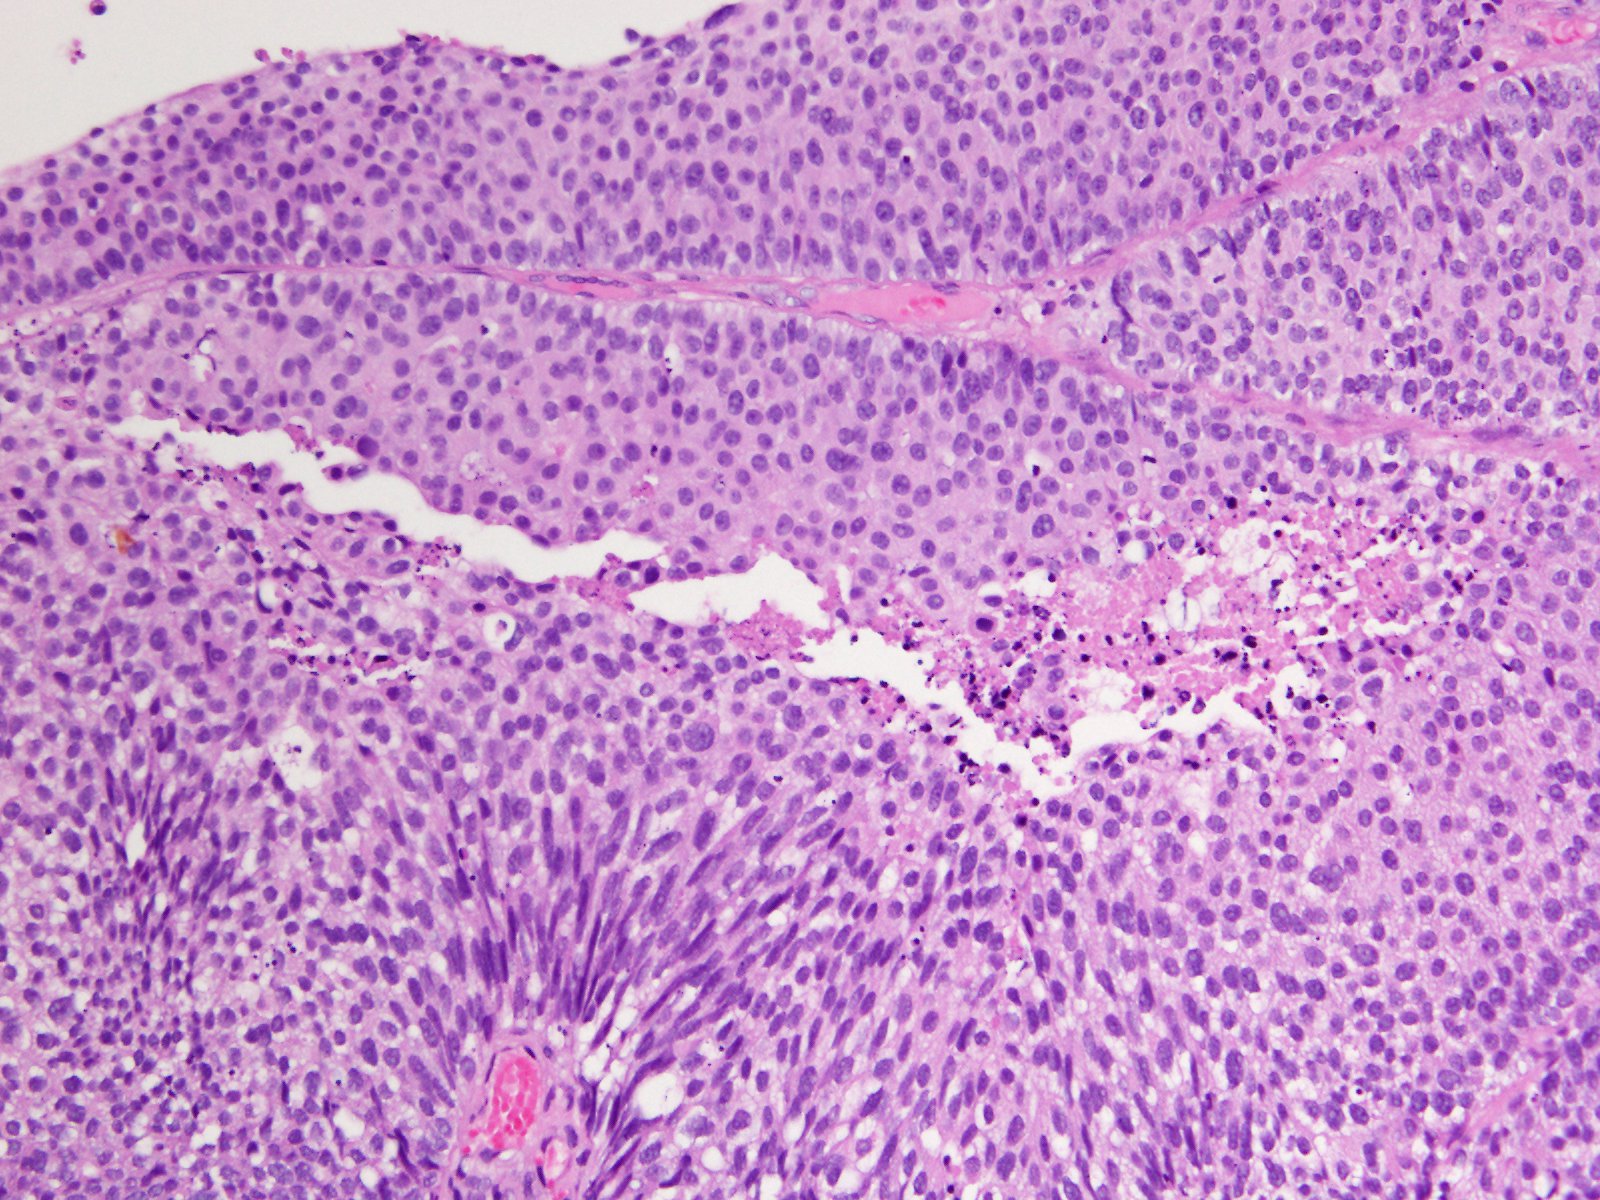

Consensus grade: High-grade papillary urothelial carcinoma (HG-PUC)

Case description (by case creator):

Papillary tumor in TUR-BT.